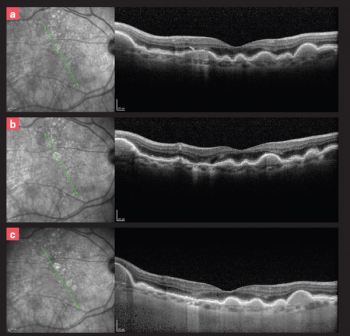

A look at the latest developments in retinal disease, including clinical trials and advanced therapies.